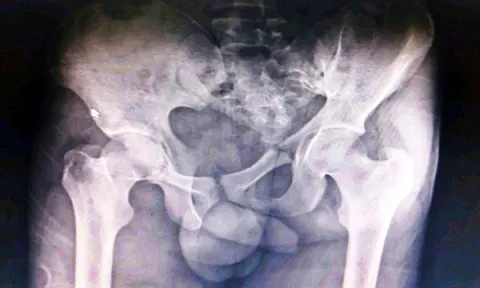

Be vigilant to spot traumatic injuries, with a low threshold for escalation